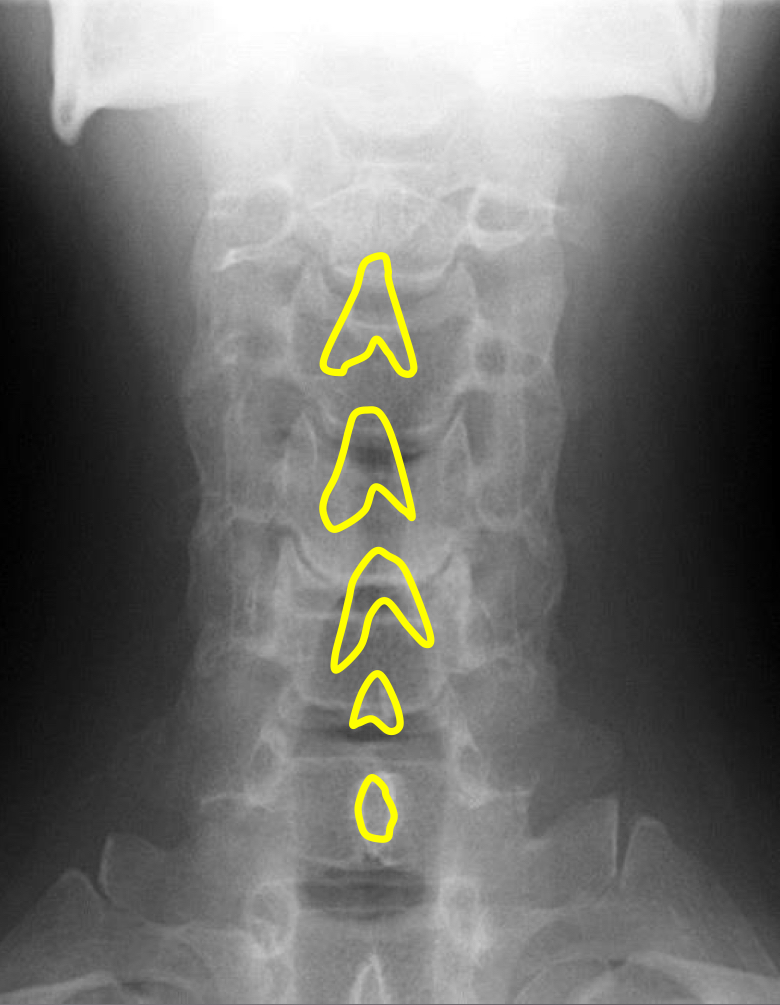

What view is this?

AP (Anterior to Posterior) Cervical

What is this?

Junction of Lamina/tip of Spinous

What is this?

Uncinate Processes

What is this?

Inferior Aspect of Vertebral Bodies